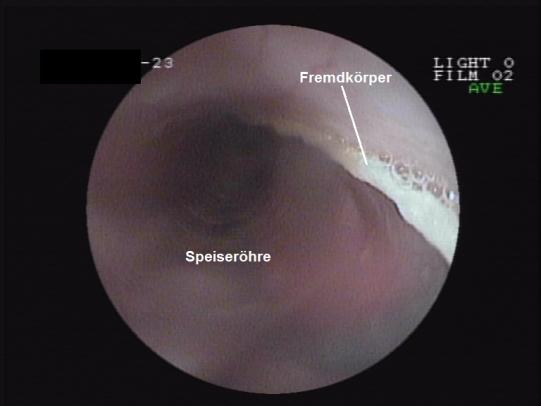

Nach Rücksprache mit den Besitzern wird zuerst eine kurze Speiseröhren- und Magenspiegelung durchgeführt. Zwar sind Magen und Oesophagus unversehrt, leider zeigt sich aber, dass die Schnur durch den Magenausgang im Dünndarm verschwindet. Nun gibt es keine andere Option mehr, als die Bauchhöhle zu eröffnen und den Fremdkörper chirurgisch zu entfernen.